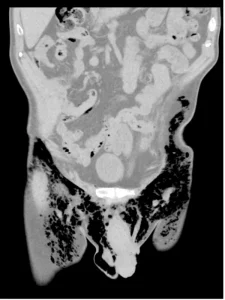

Sëmundja e pazakontë ishte për shkak të akumulimit të tepërt të ajrit në trupin e tij, i cili po ikte përmes një plage të hapur në testikujt e tij.

Mjekët përshkruan atë që ndodhi në American Journal of Case Reports, duke thënë se ata besonin se ishte rasti i parë i këtij lloji. Ka pasur raste të rralla të akumulimit të ajrit në testikuj më parë, por jo me fishkëllimë. Kjo ndodhi sepse burri i ishte nënshtruar një operacioni në atë zonë disa muaj më parë dhe kishte mbetur një plagë ku mund të dilte ajri.

Punimi përfundoi: ‘Rasti ynë i pneumoscrotum [ fishkëllimë skotale] nga pneumotoracat dypalëshe spontane të dyshuara [mushkëritë e rrëzuara] ishte i pazakontë. Pacienti ynë kishte një plagë të hapur të skrotalit nga një procedurë e fundit e skrotalit, e cila lejoi që ajri të dilte nga pjesa e tij e barkut dhe rezultoi në shqetësimin e tij’.